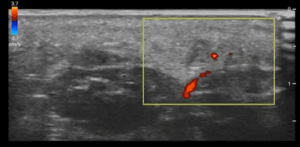

Figure 4. POCUS of soft tissues of foot revealing linear, hyperechoic FB

Figure 5. POCUS of linear FB measuring 2.46cm in long axis

Figure 6. POCUS of foot demonstrating hypoechoic collection indicative of  organising seroma deep to FB

One study examined the use of power Doppler in 25 patients with possible FBs. They provided a sensitivity of 92% for the overall detection of FBs, with 2 false-positive findings in which discrete FBs were not seen at gross inspection. Inflammation and scar tissue were present at histologic examination. Hypervascularity immediately surrounding the FB was demonstrated on power Doppler imaging in all cases. In this study, scans were performed by one of two experienced musculoskeletal radiologists rather than emergency physicians. The peripheral extremities (feet and fingers) were involved in all cases [31].